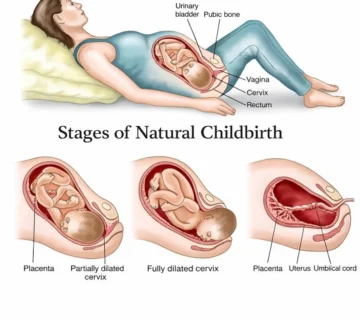

Дар ҳафтаи 24-уми ҳомиладорӣ, Шумо ба марҳилаи муҳимтарини семоҳаи дуюм ворид мешавед. Ҳаракатҳои ҷанин қавитар мешаванд, чеҳрааш равшантар мегардад ва узвҳои ҳаётан муҳими ӯ — махсусан шуш ва системаи асаб — бо суръат рушд мекунанд.

Ин ҳафта ба моҳи шашуми ҳомиладорӣ мувофиқ аст ва дар нисфи дуюми семоҳаи дуюм қарор дорад.